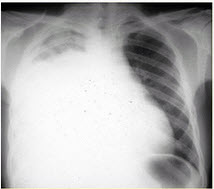

患者女,29岁。间断干咳10年余,加重4个月,伴进行性呼吸困难1个月。病程中出现双手及双足非凹陷性肿胀、双侧膝关节及双侧肘关节对称性肿痛,面部出现细小红色丘疹。体检:T36.5℃,P88次/min,R22次/min,BP110/75mmHg,SpO293%(自然)。额部、前胸及后背散在红色小丘疹,双肺呼吸音增强,双肺中下肺野可闻及爆裂音,右肺明显。胸部CT如图所示。